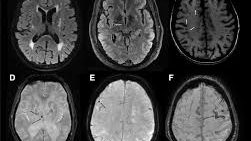

މެސެޗުސެޓްސް ޖެނެރަލް ހޮސްޕިޓަލްގެ ބްރެއިން ކެއާ ލެބްގެ އިސް ދިރާސާވެރިޔާ ޑރ. ސަންޖުލާ ސިންގް ވިދާޅުވާ ގޮތުގައި، މި ބަލިތަކުގެ އަސްލު ގުޅިފައިވަނީ ސިކުނޑީގެ ކުދި ލޭހޮޅިތަކަށް ލިބޭ ގެއްލުމާއެވެ. "ސްޓްރޯކްގެ 60 އިންސައްތަ، ޑިމެންޝިއާގެ 40 އިންސައްތަ އަދި ޑިޕްރެޝަންގެ 35 އިންސައްތައަކީ ހަމައެކަނި ދިރިއުޅުމުގެ ވައްޓަފާޅި ބަދަލުކޮށްލައިގެން ހުއްޓުވިދާނެ ކަންކަން،" އޭނާ ފާހަގަކުރެއްވިއެވެ.

މި ދިރާސާގައި ސިކުނޑިއަށް ގެއްލުންދޭ 13 އާދައެއް ފާހަގަކޮށްފައިވެއެވެ. މީގެ ތެރެއިން އެންމެ ނުރައްކާތެރި ކަމަކީ ލޭމަތިވުން އެވެ. ލޭމަތިވުމަކީ ސްޓްރޯކް ޖެހުމުގެ ފުރުސަތު ތިންގުނަ އިތުރުކޮށްދޭ ކަމެކެވެ. މީގެ އިތުރުން ހަކުރު ބަލި، ފަލަވުން، ސިގިރޭޓް ބުއިން، ނިދި މަދުވުން، އަދި އިވުމުގެ މައްސަލަތަކަކީ ސިކުނޑީގެ ދިރުން އަވަހަށް ނެތިގެންދާ ކަންކަމެވެ.